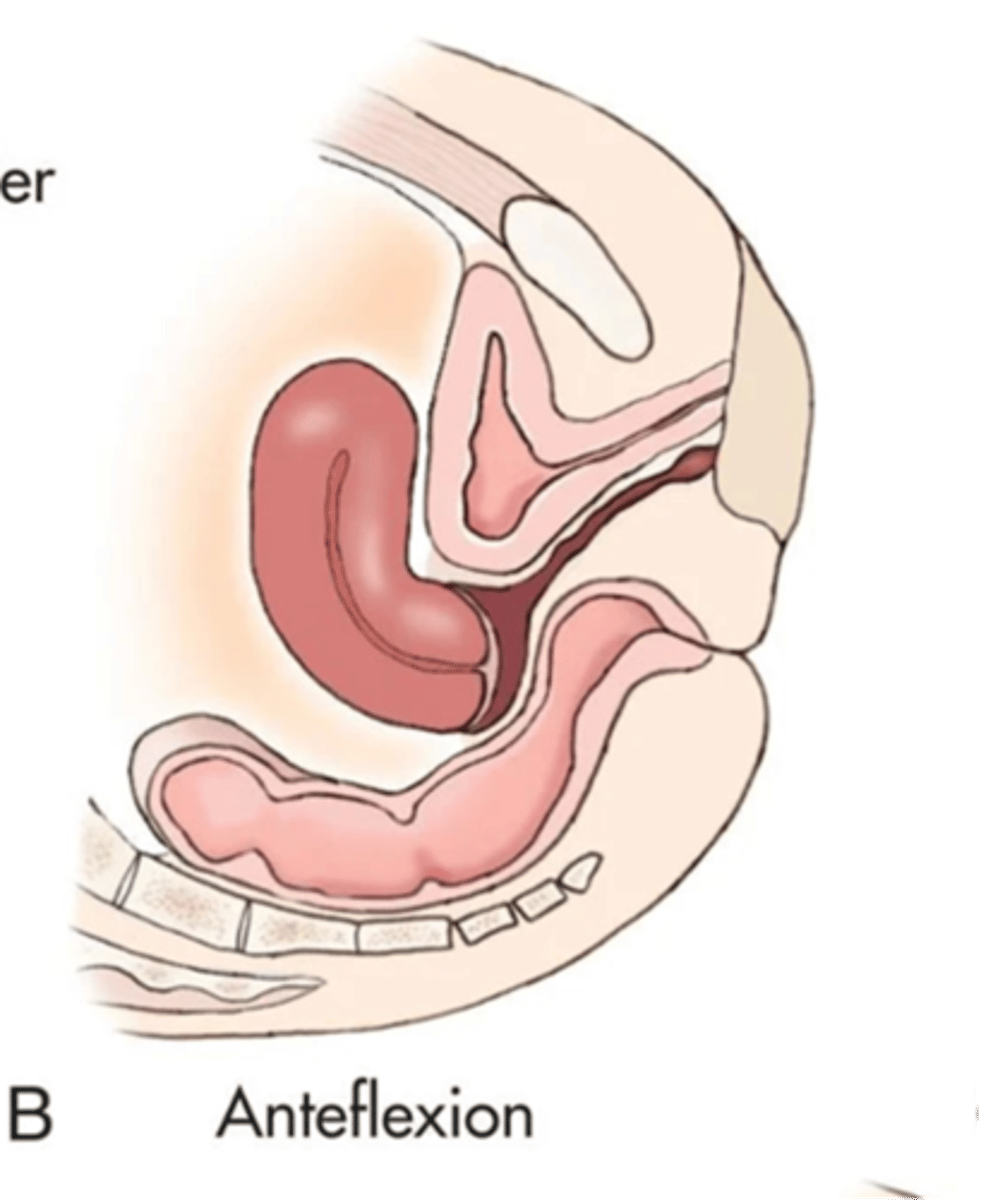

What is an anteflexed uterus?

fundus and body bend forward, cervix and vagina form 90 degree angle